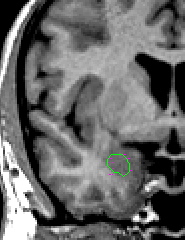

| Part III - Hippocampus appears When the ILV is first visible, it is likely that the hippocampus is present; check for your hippocampal sulci lines as well. To segment the amygdala in this area, use a contour line to define the hip-amyg area. Call up your sulci lines. Depending on the brain, you will see darker pixels that represent the ILV, or lighter pixels that represent the fimbria of the hippocampus (or both) along your sulci lines. If possible, draw a line separating the amygdala from the hippocampus along the dark pixels of ILV. Try increasing the contrast between black and white to better see this division. If after manipulating the brightness/contrast this line is not visible, draw a line that bisects your sulci lines. Then use projection lines to verify that your line really is the division between the hippocampus and the amygdala. When you are satisfied, unextract the hip-amyg outline, and extract the top portion as amygdala. | |

| Part IV - Posterior portion of the amygdala  Labeling  | |